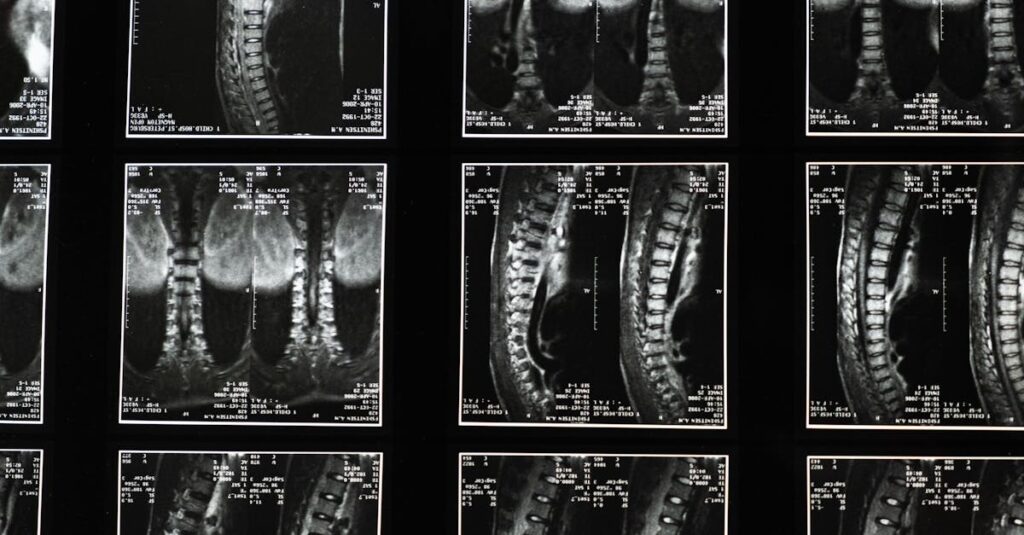

Une expertise médicale est souvent nécessaire pour établir le lien entre l’accident et la sciatique. Cette évaluation figure comme un élément clé dans le processus d’indemnisation. Le médecin expert procède à un examen physique et des tests d’imagerie, tels que des radiographies ou IRM, pour déterminer l’origine de la douleur et évaluer l’étendue des blessures.

Suite à cette évaluation, il pourra recommander un plan de traitement approprié, qui pourrait inclure la prise de médicaments, des séances de physiothérapie, voire une intervention chirurgicale si les autres traitements ne suffisent pas à atténuer la douleur. Les résultats de l’expertise médicale devront ensuite être présentés à l’assureur pour obtenir une indemnisation.